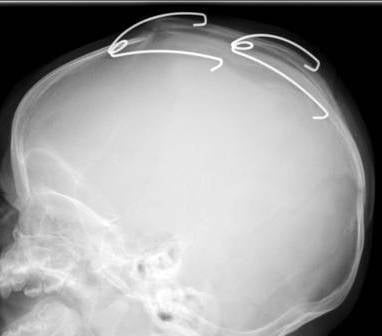

Nu hebben we het wel iedere keer over die 'veren' maar het is moeilijk uit te leggen hoe deze er uit zien en hoe ze nu zitten. De een beschrijft het als paperclips, de ander weer als 'v'tjes. Daarom hebben wij aan de dokter gevraagd hoe dat er nu precies uitziet. De dokter was zo vriendelijk de echofoto's van Vince te mailen.

De volgende foto's zijn van de eerste controle na drie weken en 4 dagen. Hier kun je goed de veren zien zitten. Ik heb het contrast van de eerste foto iets vergroot zodat je duidelijk zaagsnedes kunt zien zitten en hoever deze al wijken door druk van de veren. Ook kun je al goed zien hoe de bootvorm is afgenomen aan de achterkant.

Nogmaals, dit effect was na nog geen vier weken al bereikt, kun je nagaan wat het effect nu na twaalf weken is.